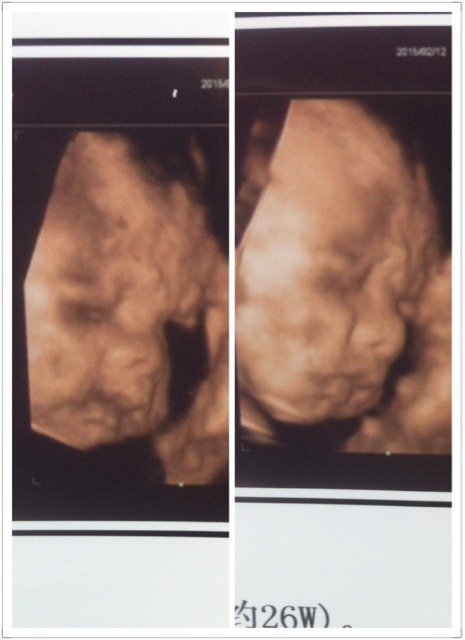

这四维看起来像男孩还是女孩姐妹们 这四维看起来像男孩还是女孩姐妹们 点击展开 随遇而安* 2015-03-09 09:41 为您推荐: 其他回答 嗯好的,, 用户5544627921 2015-03-09 14:02 好的,祝宝妈好孕 用户5544627921 2015-03-09 14:01 朋友卖的宝妈感兴趣我可以给你联系方式你了解一下可以吗 用户5544627921 2015-03-09 13:12 我也是买朋友的试剂测试的,我的两个宝宝都挺准,现在二胎是男宝,好开心的 用户5544627921 2015-03-09 11:15 一般的医生都看不出来,需要专业的B超人员动态下才能辨别。 qq286550079 2015-03-09 11:10 加载更多 相关问题 四维归来,终于拍到脸了,小家伙高鼻梁小嘴巴的 大家快看看像男孩还是女孩阿…